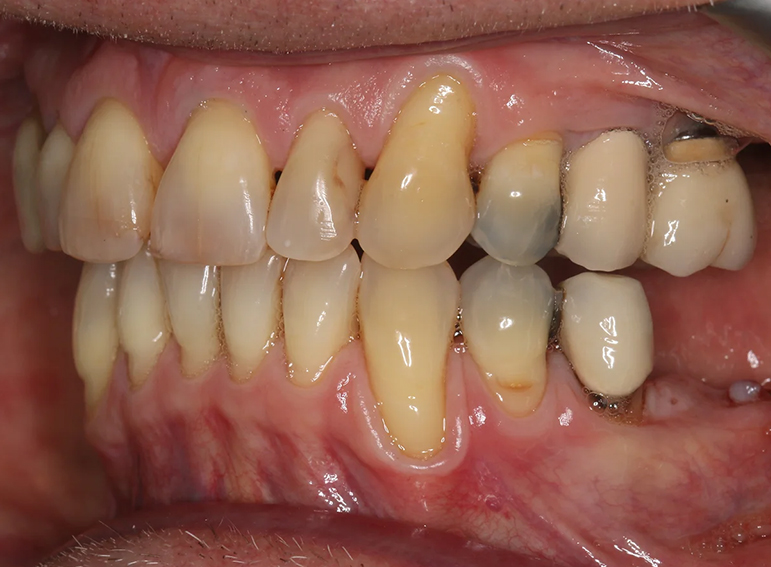

Case 18 – Prosthodontics

Extraction of failed bridge and temporary denture.